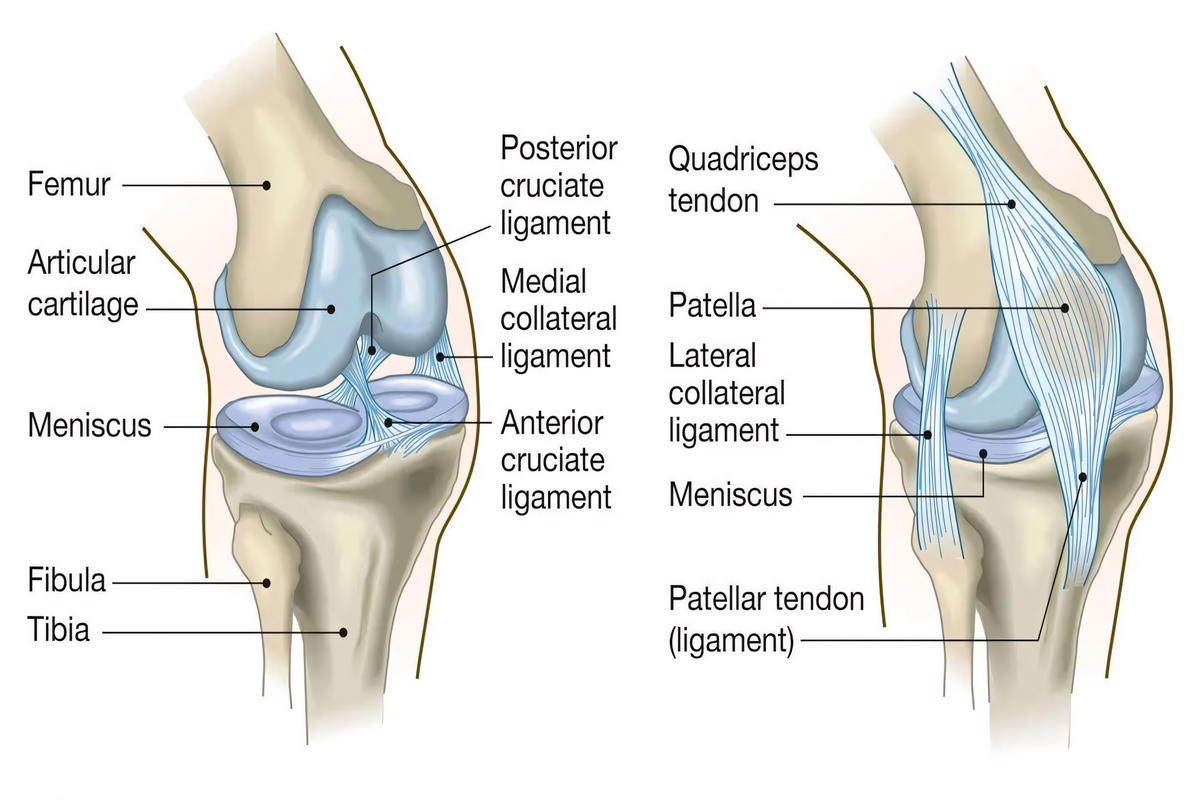

Ο έσω πλάγιος σύνδεσμος (MCL) βρίσκεται στην εσωτερική πλευρά του γόνατος και εμποδίζει την απόκλιση της άρθρωσης προς τα μέσα. Ο έξω πλάγιος σύνδεσμος (LCL) εντοπίζεται στην εξωτερική πλευρά και προστατεύει από δυνάμεις που ωθούν το γόνατο προς τα έξω.

Ο τραυματισμός του έσω πλαγίου συνδέσμου είναι συχνότερος, ενώ η ρήξη του έξω πλαγίου συνδέσμου συνήθως σχετίζεται με σοβαρότερες κακώσεις και συχνά συνοδεύεται από βλάβες άλλων συνδέσμων, όπως ο πρόσθιος χιαστός σύνδεσμος.

Ακτινογραφία γόνατος για αποκλεισμό κατάγματος ή αποσπαστικής βλάβης.

Μαγνητική τομογραφία (MRI), η οποία αποτελεί την πιο αξιόπιστη εξέταση για τον καθορισμό του βαθμού ρήξης και τον έλεγχο συνοδών κακώσεων (χιαστοί σύνδεσμοι, μηνίσκοι).